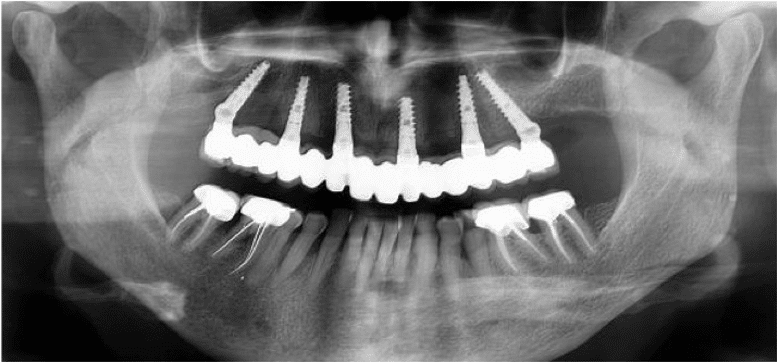

Un implant dentaire est une racine artificielle placée par le chirurgien-dentiste dans l’os alvéolaire de l’un des maxillaires en remplacement de la racine d’une dent extraite et servant de support à une prothèse.

Sa forme est généralement cylindrique ou légèrement conique, ressemblant à une vis, en titane ou en zircone, avec une connexion au niveau supérieur, à l’emplacement de la gencive, pour permettre la pose d’un élément prothétique par vissage ou scellement. Son diamètre varie entre 3 et 5mm et sa longueur entre 6 et 15mm.

Cette technique sûre et efficace s’appuie sur des données scientifiques avec un recul clinique de plus de 20 ans. La pose d’un implant, réalisée sous anesthésie locale, est totalement indolore. Elle se pratique au cabinet dentaire ou en clinique. Le choix se fait en fonction de l’emplacement, de la quantité d’os disponible, et des éléments anatomiques environnants à partir d’un examen radiologique et scanner de la zone à implanter.

Dans certains cas une mise en charge immédiate est possible, c’est à dire la mise en place d’une prothèse transitoire le jour de la chirurgie.